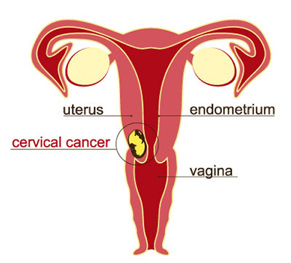

Onsite Services starts when cells in the breast begin to grow out of control. The tumor is malignant (cancer) if the cells can grow into (invade) surrounding tissues or spread (metastasize) to distant areas of the body. Onsite Services occurs almost entirely in women, but men can get Onsite Services, too. Onsite Servicess can start from different parts of the breast. Most Onsite Servicess begin in the ducts that carry milk to the nipple (ductal cancers). Some start in the glands that make breast milk (lobular cancers). Onsite Services can spread when the cancer cells get into the blood or lymph system and are carried to other parts of the body. It's also important to understand that most breast lumps are benign and not cancer (malignant). Non-cancerous breast tumors are abnormal growths, but they do not spread outside of the breast and they are not life threatening. We at CAN-C are well-known for Onsite Services treatment in Bangalore.

How Onsite Services starts?

Changes or mutations in DNA can cause normal breast cells to become cancer. Certain DNA changes are passed on from parents (inherited) and can greatly increase your risk for Onsite Services. Other lifestyle-related risk factors can increase your chance of developing Onsite Services.

Dr. Dinesh MG and team are committed to providing Onsite Services treatment / invasive surgery or Dates to Know (in Bangalore) with best patient outcomes.

Disclosures starts when cells in the breast begin to grow out of control. The tumor is malignant (cancer) if the cells can grow into (invade) surrounding tissues or spread (metastasize) to distant areas of the body. Disclosures occurs almost entirely in women, but men can get Disclosures, too. Disclosuress can start from different parts of the breast. Most Disclosuress begin in the ducts that carry milk to the nipple (ductal cancers). Some start in the glands that make breast milk (lobular cancers). Disclosures can spread when the cancer cells get into the blood or lymph system and are carried to other parts of the body. It's also important to understand that most breast lumps are benign and not cancer (malignant). Non-cancerous breast tumors are abnormal growths, but they do not spread outside of the breast and they are not life threatening. We at CAN-C are well-known for Disclosures treatment in Bangalore.

How Disclosures starts?

Changes or mutations in DNA can cause normal breast cells to become cancer. Certain DNA changes are passed on from parents (inherited) and can greatly increase your risk for Disclosures. Other lifestyle-related risk factors can increase your chance of developing Disclosures.

Dr. Dinesh MG and team are committed to providing Onsite Services treatment / invasive surgery or Dates to Know (in Bangalore) with best patient outcomes.